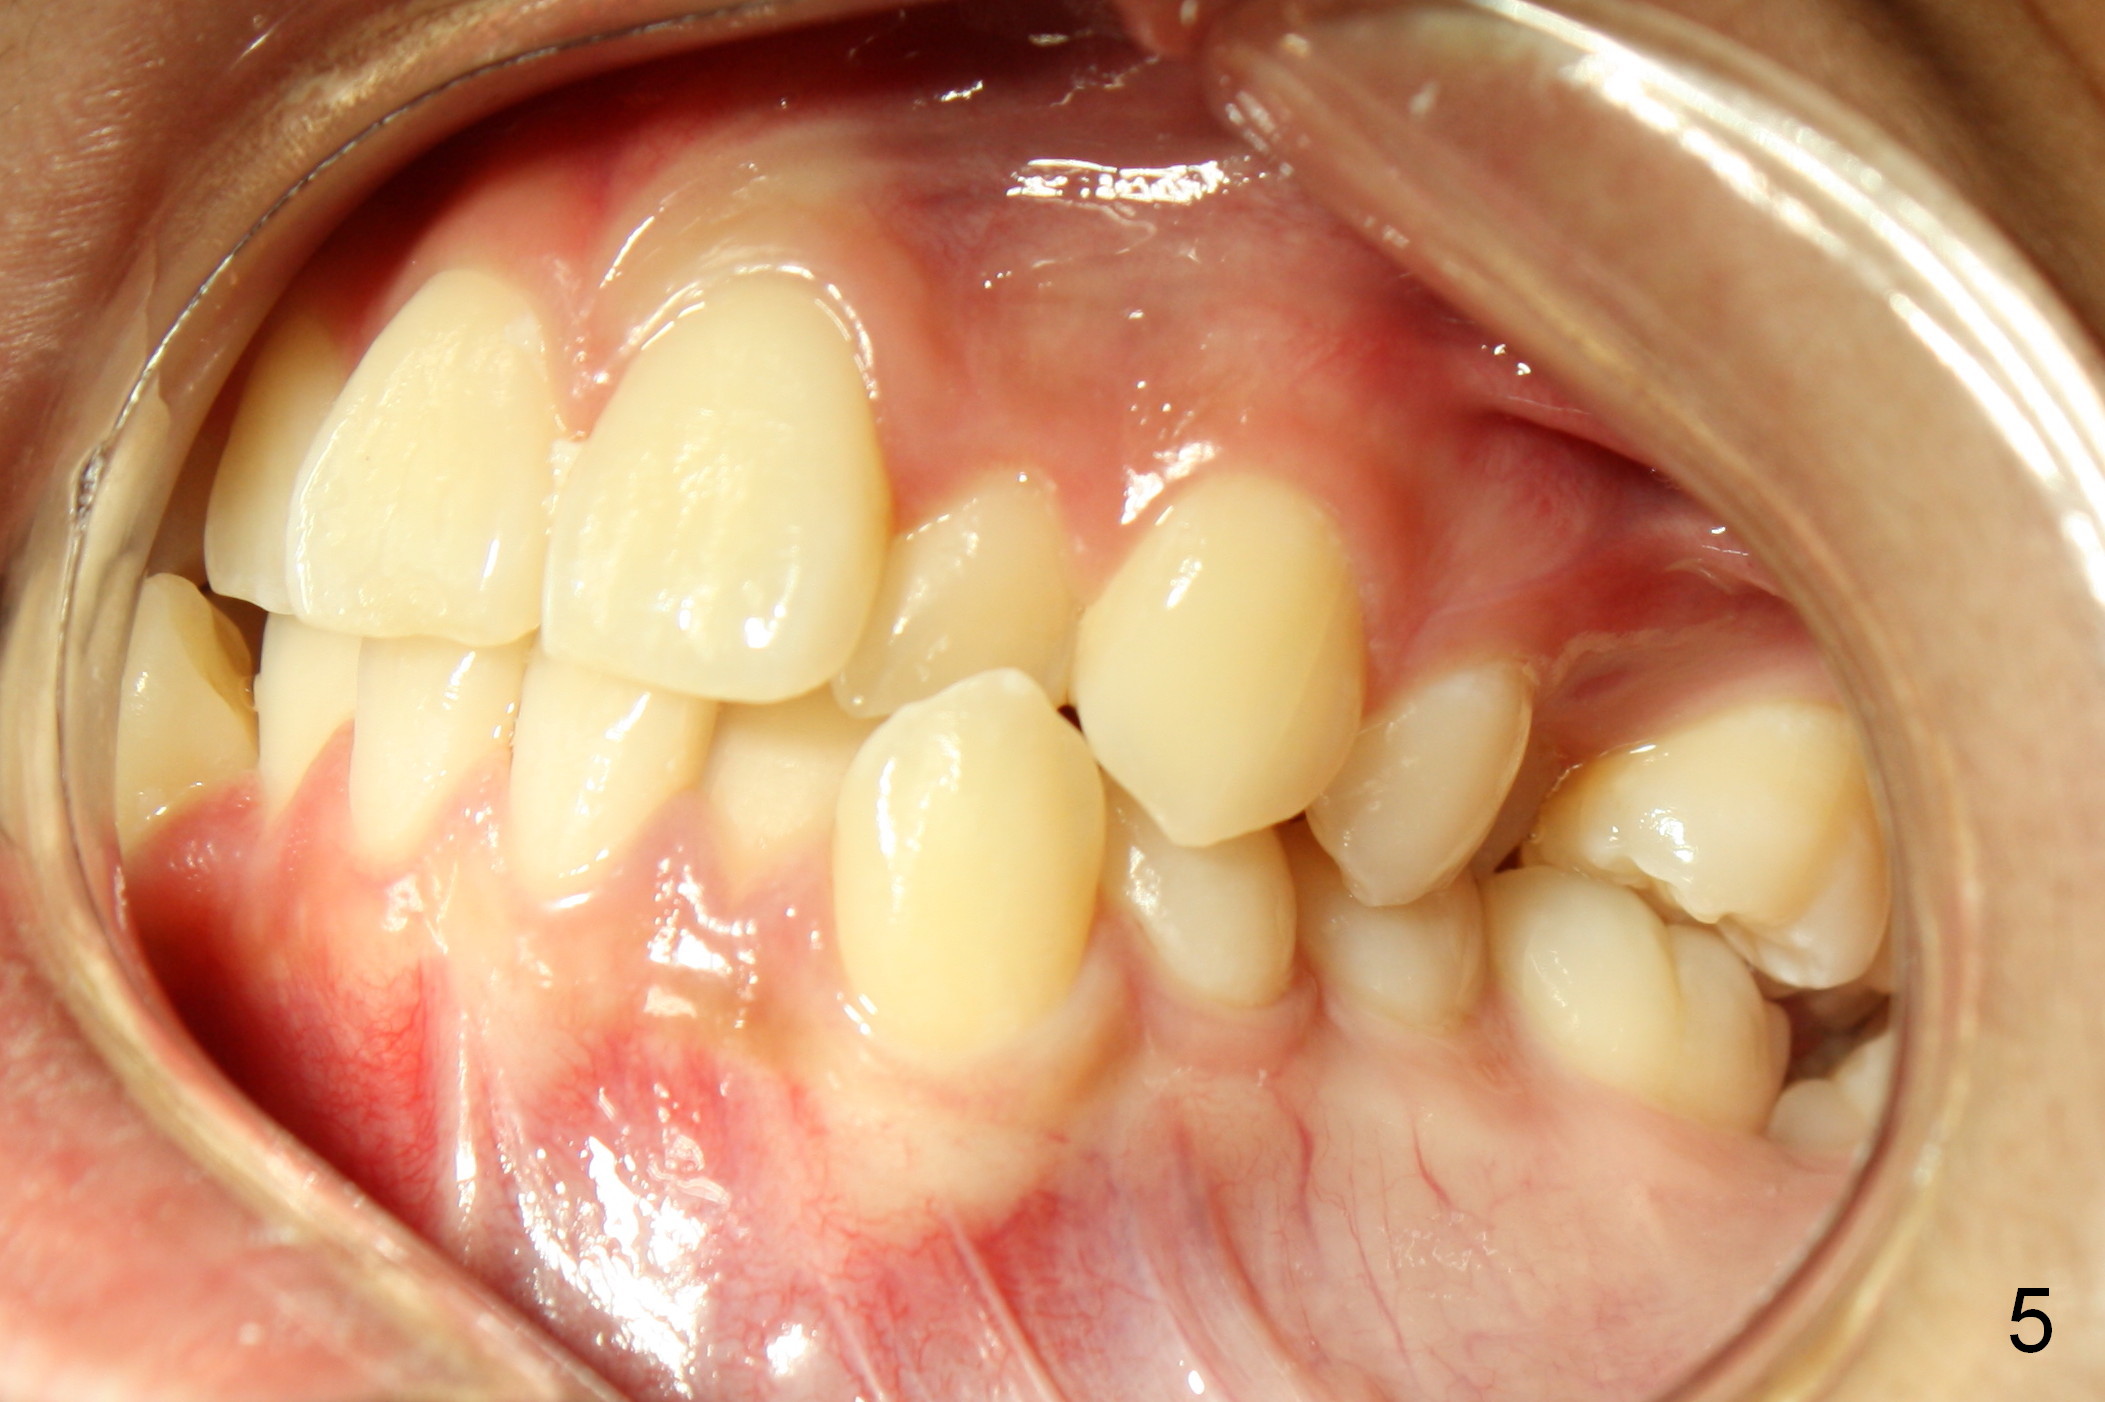

When taking photos for the lateral view of the occlusion (Fig.3, retract the corner mouth as back as possible using proper sized cheek retractors (single or double, child or adult) or a mouth mirror. The focus should be on the posterior teeth, showing interdigitation. That is move the camera to the side of the face.

Lighting should be double checked (Fig.1,2).